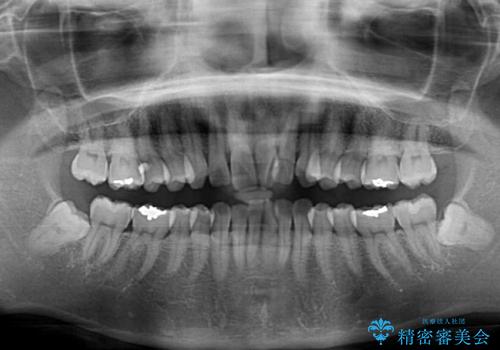

- 前歯の捻れと、それに伴う口元の突出感を気にして来院された患者様です。

早く治療を終えたいとのことで、ワイヤー装置による矯正治療を行うこととしました。

- 費用(概算)

- 治療費の目安: 90万円費用は治療当時の料金となります

上顎前歯の叢生が解消されると出っ歯になることが分かっていたので、両側奥歯付近にアンカースクリューを入れ、出っ歯を改善するためのゴムかけを行いました。

ゴムかけを頑張っていただいたので、当初の予定通り、1年強で治療を終えることができました。